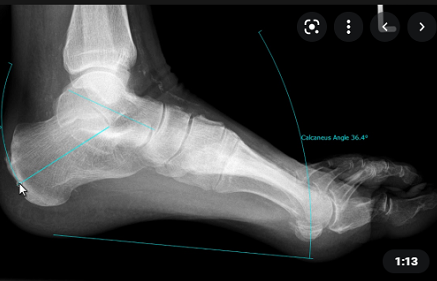

3. Bàn chân bẹt

Chức năng "Flatfoot" cho phép đo kích thước chẳng hạn như góc xương gót, sên - bàn hoặc sên – gót chân.

Các thông số này có thể được dùng để đưa ra đánh giá bổ sung về tình trạng bệnh lý.